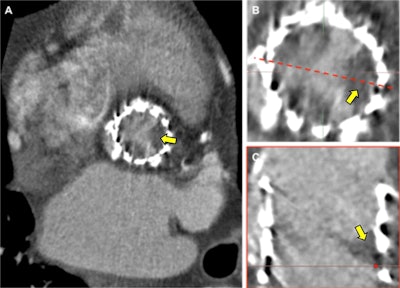

Transcatheter aortic valve replacement hypoattenuated leaflet thickening several months after transcatheter aortic valve implantation (26 mm Spaien 3, Edwards Lifesciences). Elevated transprosthesis pressure gradients were observed on echocardiography, and 4D cardiac CT was performed (A). Hypoattenuation of all three prosthesis cusps was present with a restricted excursion of the leaflets during ventricular systole (B). Laminar deposition of low attenuation material on the aortic aspect of the prosthesis results in the thickened appearance of the leaflet (C). Resolution with anticoagulation and restoration of normal leaflet motion is observed with this CT finding suggesting it may represent subacute thrombus. All images courtesy of BIR.In the research field, the group is looking at using precision-imaging techniques in a number of different cardiovascular diseases. For instance, with coronary artery disease, clinicians know that patients who have experienced a heart attack have a 20% chance of having another heart attack in the next five years -- despite doctors providing the best evidence-based care.